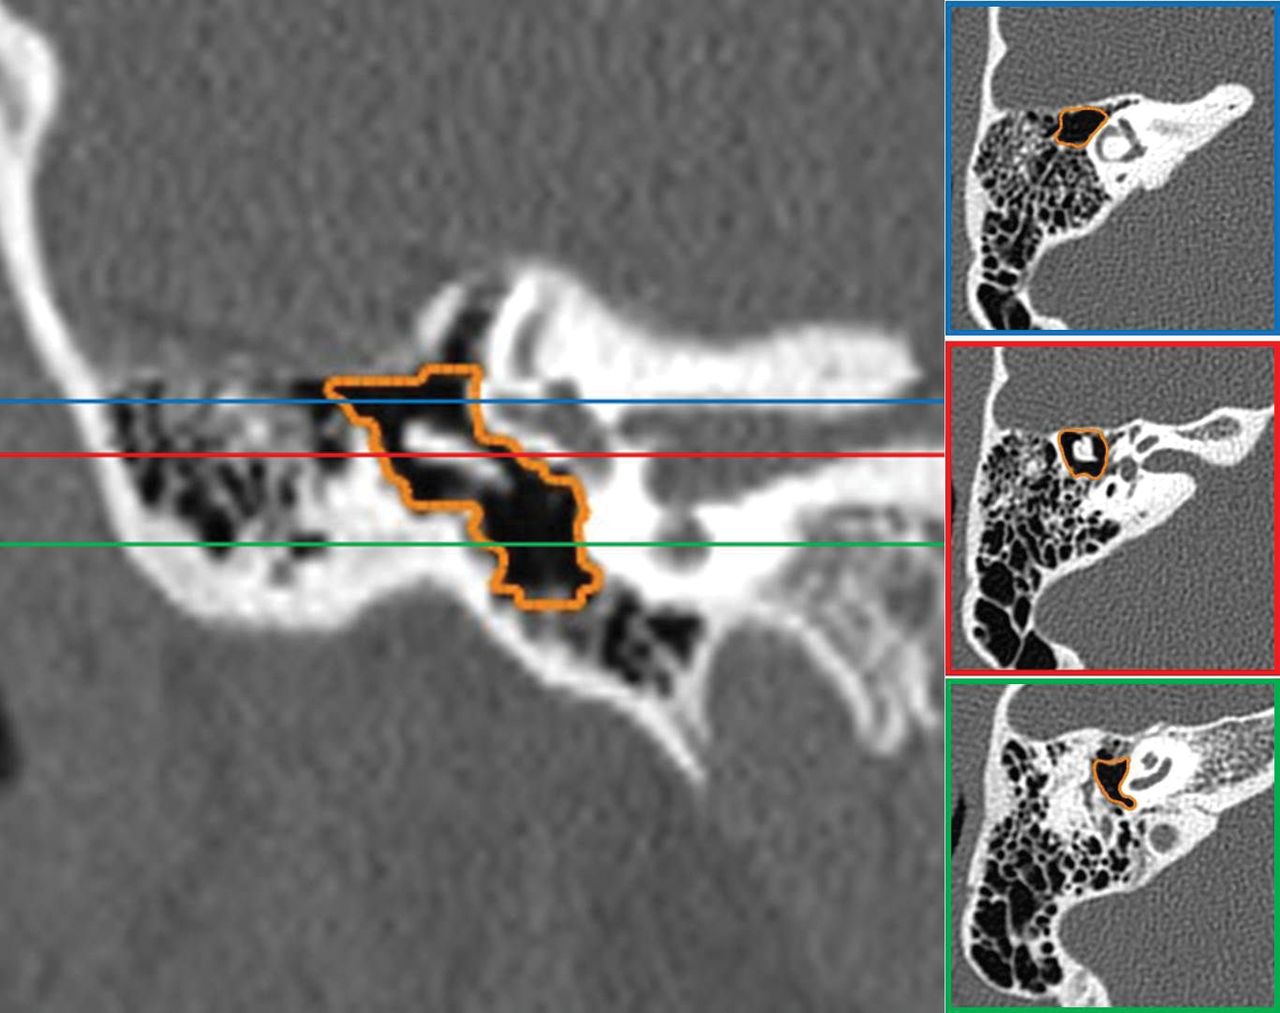

An atretic ear with middle ear volume of 251 mm3 and a J-score of 7. Coronal CT reconstruction (left) and corresponding axial CT images (right) in different regions of the middle ear demonstrate accurate semiautomated segmentation of the middle ear space.

An atretic ear with middle ear volume of 362 mm3 and a J-score of 8. Coronal CT reconstruction (left) and corresponding axial CT images (right) in different regions of the middle ear demonstrate accurate semiautomated segmentation of the middle ear space.

A normal ear with middle ear volume of 592 mm3. Coronal CT reconstruction (left) and corresponding axial CT images (right) in different regions of the middle ear demonstrate accurate semiautomated segmentation of the middle ear space.